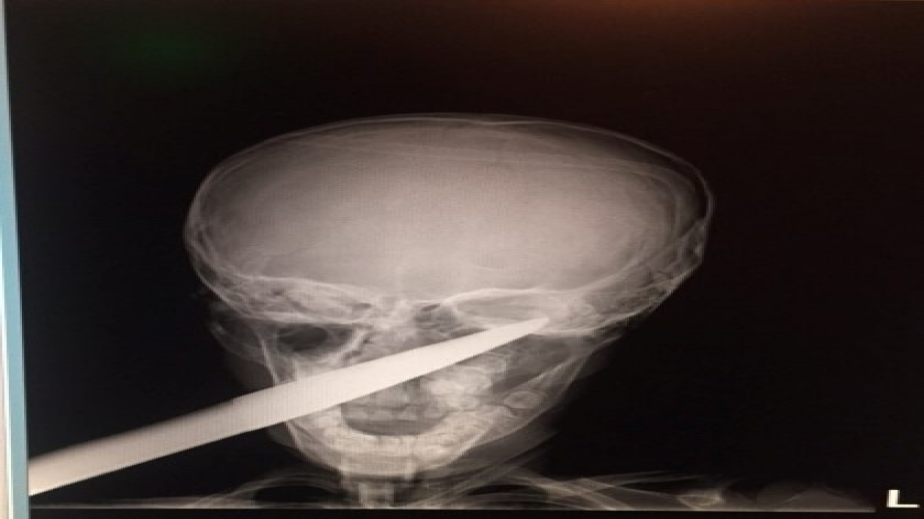

7-годишно момче със забита в главата градинска ножица беше спасено в УМБАЛ-Бургас. Това съобщиха от пресслужбата на лечебното заведение, пише Новини.бг.

По думите на родителите, детето паднало върху инструмента, докато си играело в градината. Ръждясалото острие минало през цялата буза и опряло в черепа зад окото. "Още няколко милиметра и изходът щеше да е фатален", коментират дежурните лекари.

Веднага са направени всички образни изследвания и е свикан екип за спешна операция. Следват няколко дни възстановяване в отделенията по реанимация и УНГ и от вчера момчето си е вкъщи. "В цялата си над 30-годишна практика не съм виждал подобна травма. Оприличавам я на нараняване от военно време, каквито наранявания в днешни дни са рядкост. Острието на ножицата прилича на копие, на щик. В хода на операцията то е извадено много бавно, кървенето е овладяно, наложи се и кръвопреливане", коментира УНГ-специалистът д-р Даниел Петков, който извършва операцията.

Щастливият изход е резултат от екипната работа на Спешно отделение в лицето на дежурния д-р Светослав Тодоров, анестезиолога д-р Валентин Кравченко, както и отделенията по образна диагностика и детски болести.

Случаят ще бъде докладван на медицински научен форум. Причината за травмата - градинската ножица с размер около 70 см, се пази за спомен в УНГ-отделението на Бургаската болница.